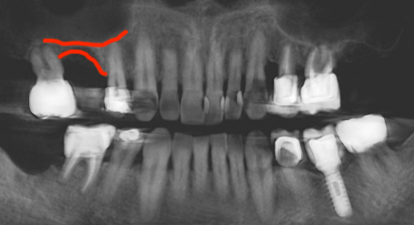

Panoramic dental X-ray showing with red markings highlighting bone growth after an open sinus lift.

After

Open Sinus Lift

to prepare for implant placement